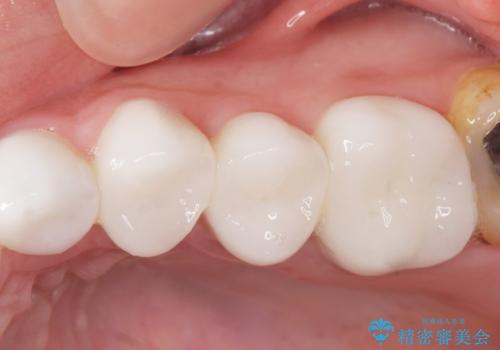

綺麗な仕上がりにご満足下さいました。

奥歯の咬み合わせも良くなったと喜んで頂けました。

患者様の理想とする韓流アイドルの写真を技工士さんに送り、最終的なクラウンの形や色をできるだけ理想に近づけられるよう努めました。

クラウンの種類:オールセラミッククラウン スタンダード